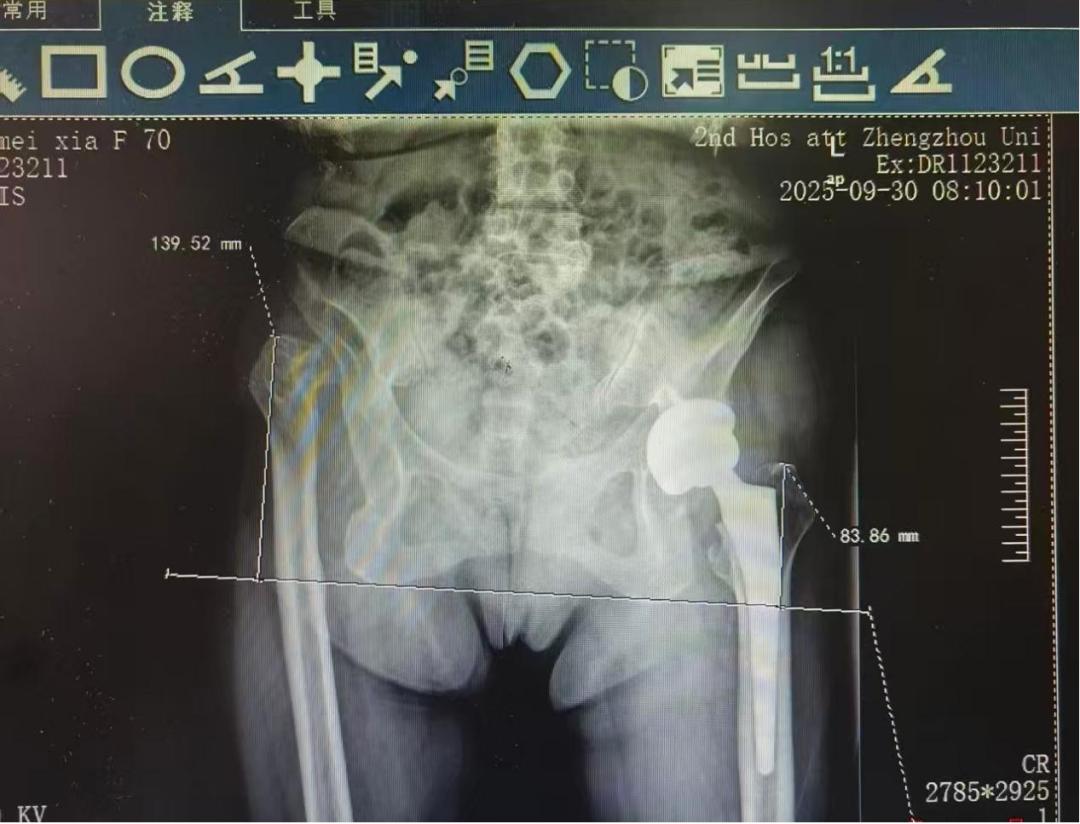

这台凝聚着智慧与勇气的手术最终大获成功。术后,李女士的双腿终于等长,各方向活动度良好,且没有任何神经损伤的迹象。

术后患者双腿等长